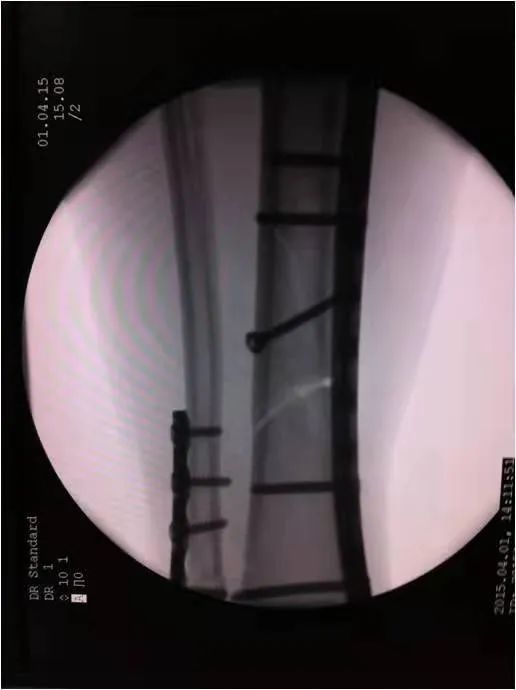

如采用傳統(tǒng)手術需大范圍剝離軟組織,手術切口在18公分,損傷面大,影響骨折愈合。經過科內術前討論后與患者及家屬溝通后,呂國福主任決定行小切口微創(chuàng)鈦板植入內固定手術治療,術中植入內固定物并剝離軟組織,此方法對周圍皮膚破壞小,手術切口最小僅0.5公分,極大降低皮膚壞死及后期出現(xiàn)骨不連發(fā)生幾率,從而達到解剖復位。

在急診科,檢驗科,麻醉科共同努力下,僅用一小時完成整個手術,術中出血量少、過程順利,手術非常成功。術后,呂國福主任數(shù)次查房,仔細查看患者的傷口愈合情況,關心患者的心理狀態(tài),為患者樹立信心,鼓勵患者進行功能鍛煉。